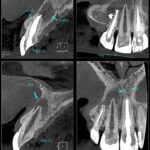

Durante a visita, o dentista pode solicitar exames de imagem, como a radiografia panorâmica, para comprovar se o dente está somente incluso (ou dentro do osso, muito comum com os dentes do siso) – e que pode não caracterizar uma agenesia – ou a sua real ausência.